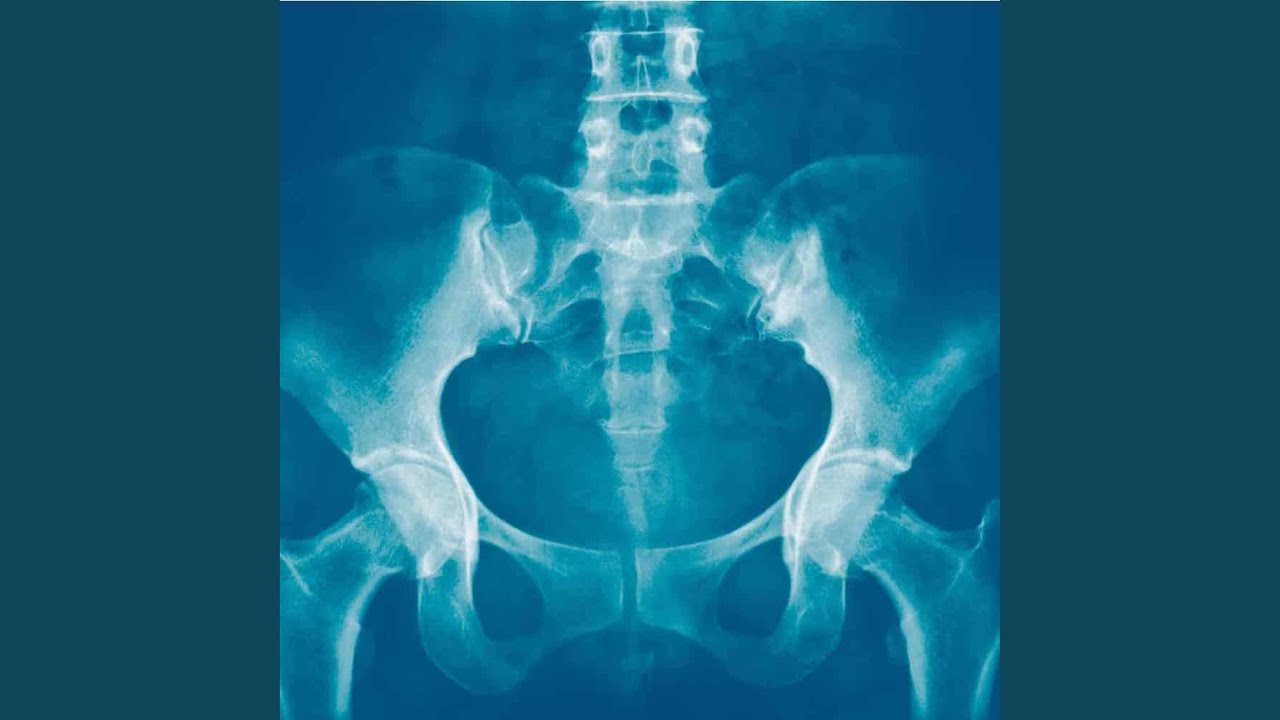

Osteomyeliitti pubisymfysitis, jonka aiheuttaa Streptococcus dysgalactiae -bakteeri. Toisin sanoen Illalla on mikro-organismien aiheuttama infektio nivelessä, joka yhdistää kaksi häpyluuta.

Osteomyeliitti, vaikka sitä ei paljon käsitellä mediassa, on yleisempää kuin luulemme. Itse asiassa useissa espanjalaisissa sairaaloissa, mukaan lukien Val d’Ebron, jossa Illa on hoidossa, on osastoja osteoartikulaaristen infektioiden hoitoon. Tässä tapauksessa epätavallisempaa on taudin sijainti. ”Suurin osa osteomyeliitin tapauksista esiintyy potilailla, joille on tehty virtsarakon tai muun luun kanssa kosketuksissa olevan ja infektioon alttiin elimen leikkaus”, hän selittää.